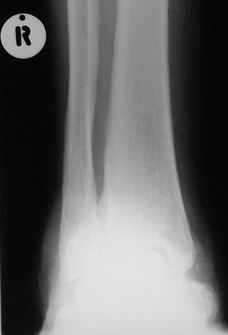

После меня выступал с новыми находками для своей коллекции Эмануэл Лакью Тесема, хирург-ортопед из Эфиопии: Мне понравились его находки:

Кто шустрый - при какой патологии встречается так называемые "суставы Шарко"? Второе приобретение доктора Эмануэла мне понравилось своим романтическим названием: Candle bone - <кость-в-виде-оплывающей-свечи> : Просто редкая патология: